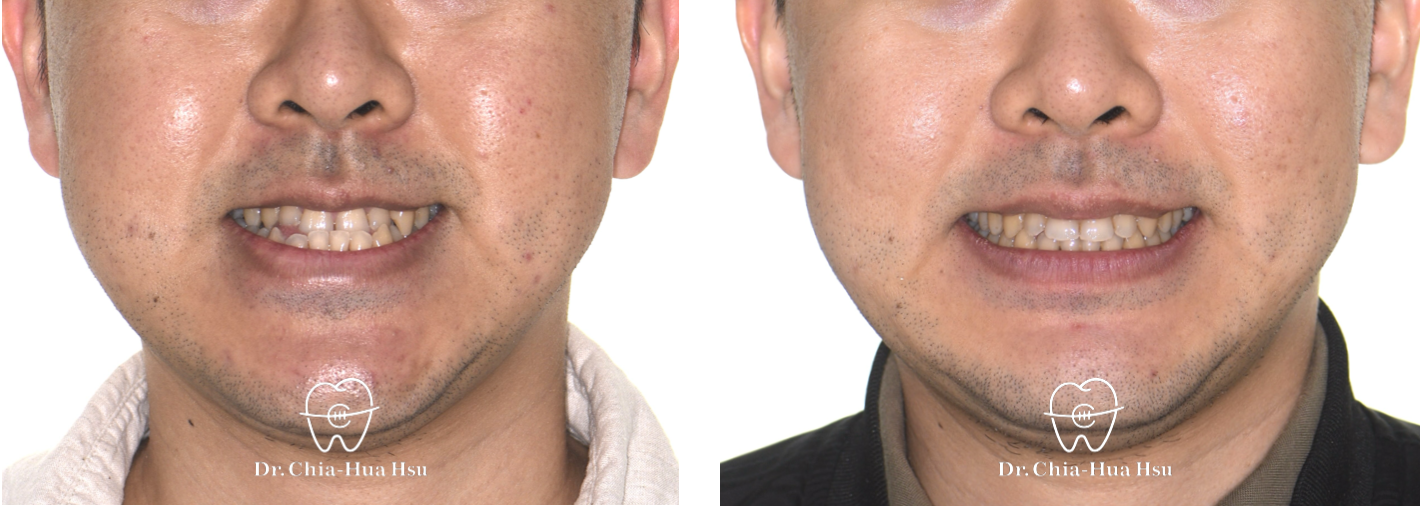

- 病患主訴:牙齒咬合不正、下巴戽斗。

- 治療結果:外觀更和諧,笑容更自信。

治療前

治療後